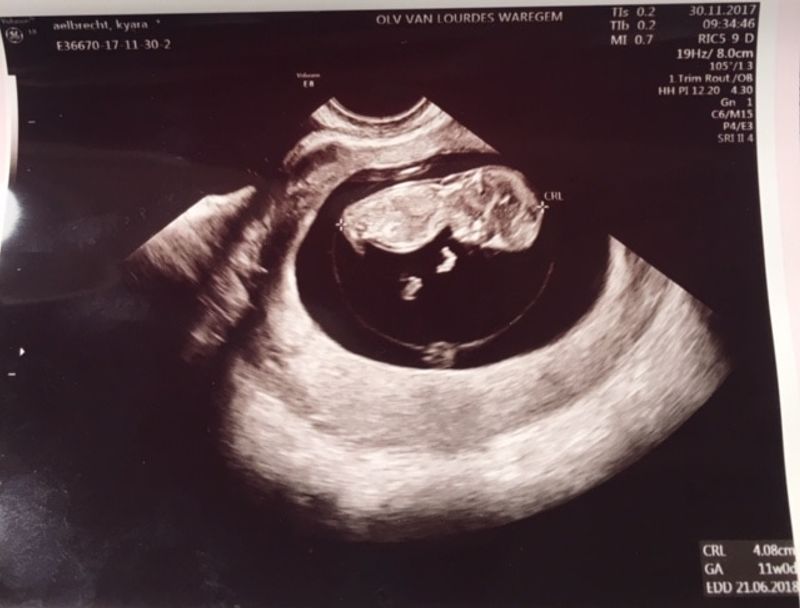

Ik had een fantastische zwangerschap, kon nu en dan ook wel eens klagen dat ik misselijk of moe was, maar ik heb zo genoten om mijn kindje te dragen al die maanden. Zwanger worden ging iets sneller dan verwacht, iets sneller dan gepland, maar we wilden graag een kindje. We wilden graag een gezinnetje zijn.